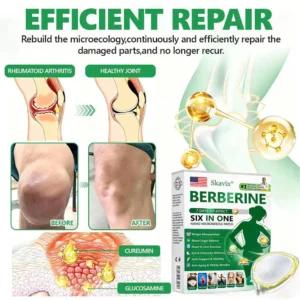

Powerful Ingredients, Proven Results

Supports natural cellular balance and helps maintain overall body wellness.